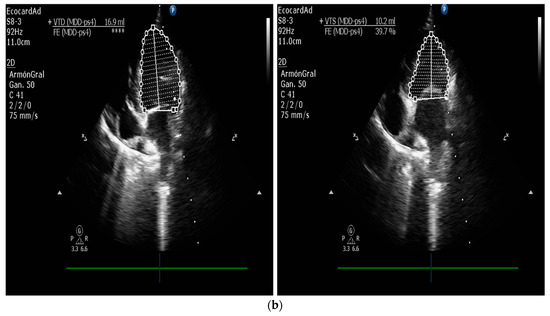

5.1.1. Measurement of Left Ventricular Volume by Simpson’s Method of Disks and Left Ventricular M-Mode

| Measurement of Left Ventricular Volume | M-mode echocardiography is widely used in canine cardiology, but its utility is debated. American Society of Echocardiography recommends against using linear measurements in the human patient. SMOD is recommended [100,102,103]. |